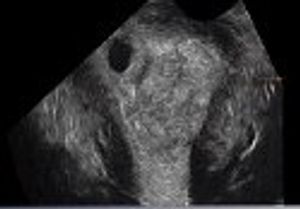

Postabortal placental polyps and uterine arteriovenous malformations can look identical on ultrasonography. Read how saline instillation sonohysterography helped discern the diagnosis.